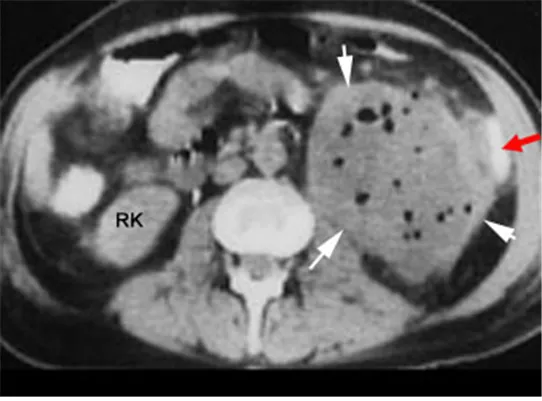

62세 여성이 좌측 결장절제술을 받은 후 복부 좌측 하부에 국한된 압통과 반발압통을 동반한 종괴가 만져졌다. 혈압은 115/75 mmHg, 체온은 38.1°C, 맥박은 102회/분, 호흡은 18회/분으로 측정되었다. 복부 CT 스캔 결과가 첨부되어 있다. 이 환자의 적절한 치료 방법은 무엇인가?

복부수술 후에 발생한 발열, 압통과 반발압통을 동반한 종괴는 복강내농양을 시사한다. CT에서도 low density mass가 air bubble과 함께 보이는 부분은 농양의 fluid collection으로 볼 수 있다. 치료는 경피적 배농과 항생제 투여이다.